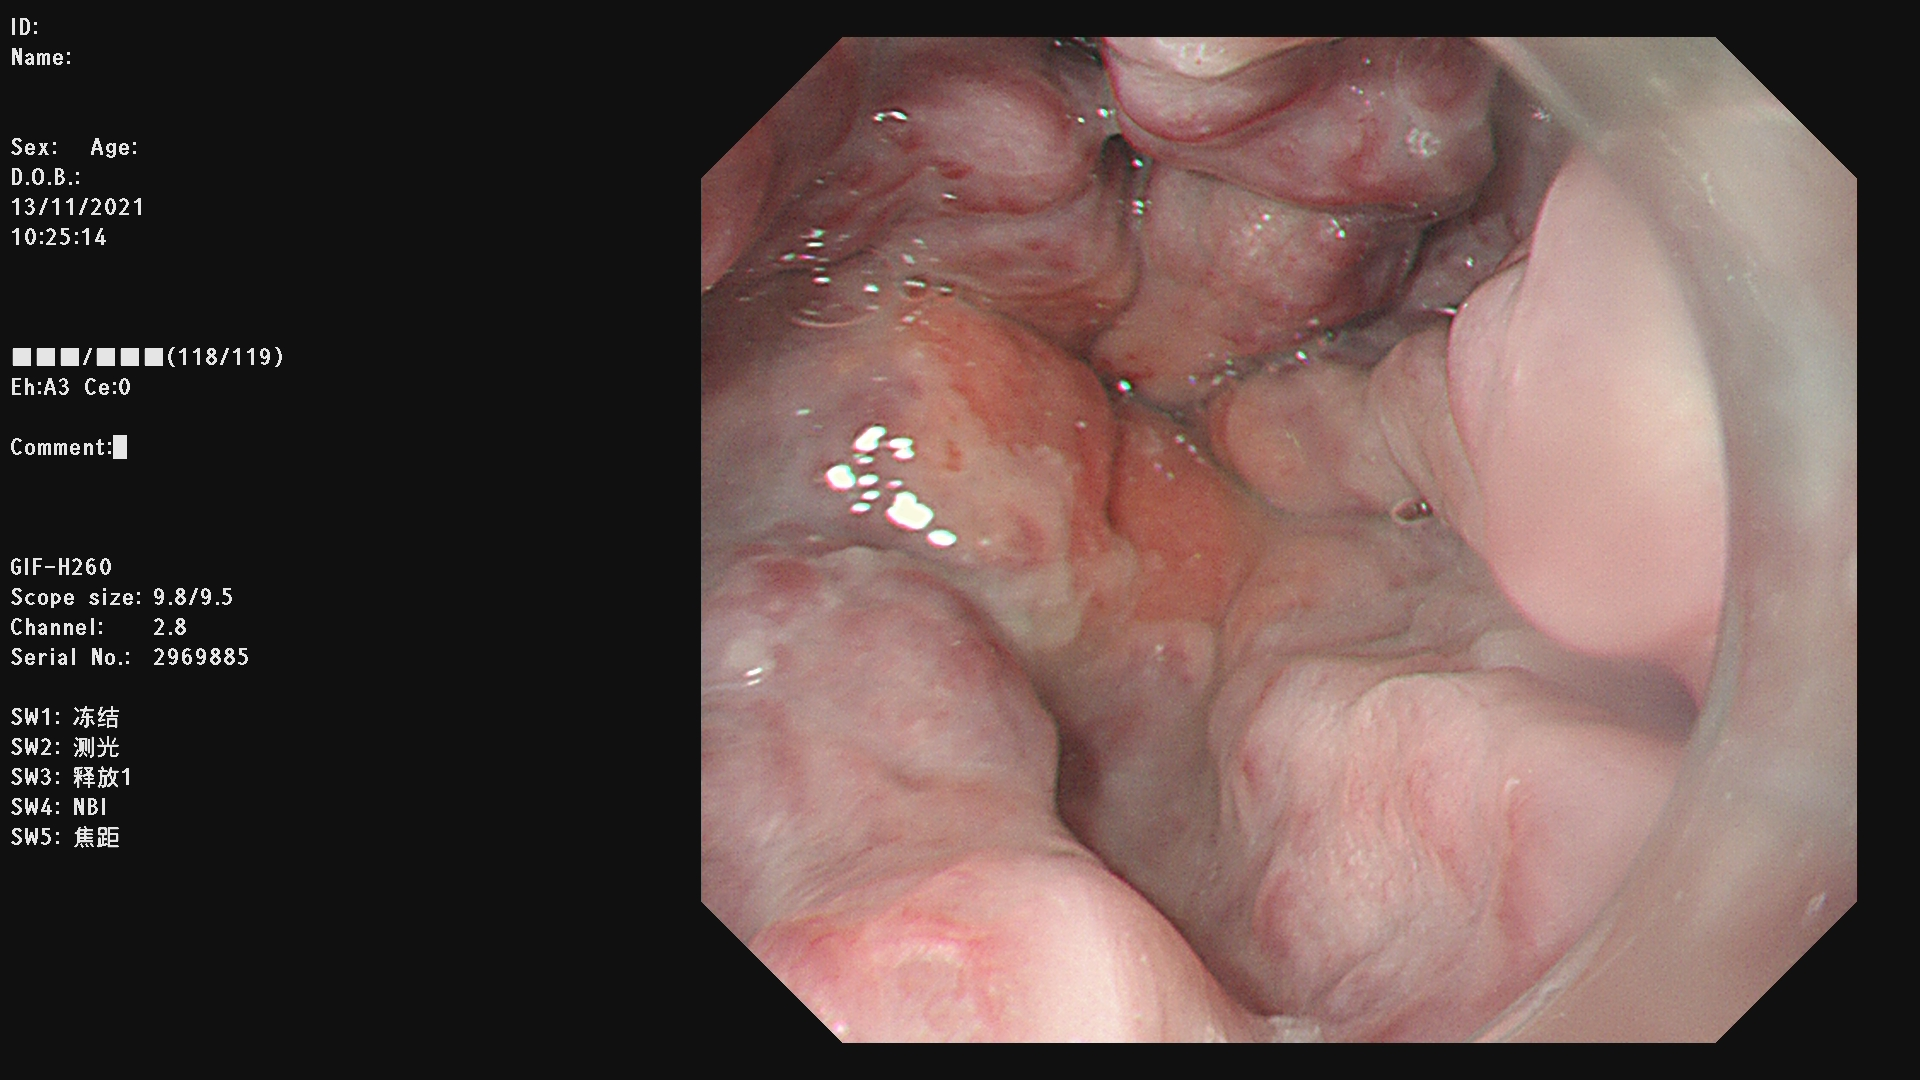

内镜下硬化术(EIS)是通过内镜下注射硬化剂和/或组织胶治疗急性食管胃底静脉曲张破裂出血及预防再出血的方法。

适应症:1.食管静脉曲张破裂出血,有出血史者预防再次出血,或重度食管静脉曲张无出血史者预防初次出血。2.胃底静脉曲张破裂出血。

例二: